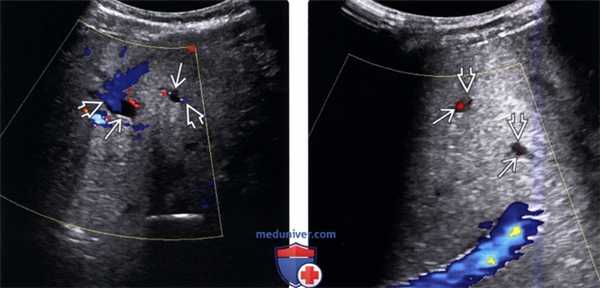

Допплеровское ультразвуковое исследование органов брюшной полости 40-летней женщины с болезнью Ходжкина, у которой признаки веноокклюзионной болезни манифестировали на 11 день после трансплантации костного мозга.

Выявляется нарушение кровотока в области портальной вены.

(Левый) При цветовой допплерографии печени кровоток в воротной вене не определяется. В левой ветви воротной вены кровоток гепатофугальный, тогда как в правой ветви воротной вены отмечается гепатопетальный кровоток.

(Правый) Энергетическая допплерография у того же пациента. Кровоток в воротной вене настолько замедлен, что он не визуализируется даже с помощью энергетической допплерографии. Серошкальное сканирование в реальном времени (не представлено) могло продемонстрировать замедленный кровоток в воротной вене за счет движения «монетных столбиков».г) Клинические особенности: